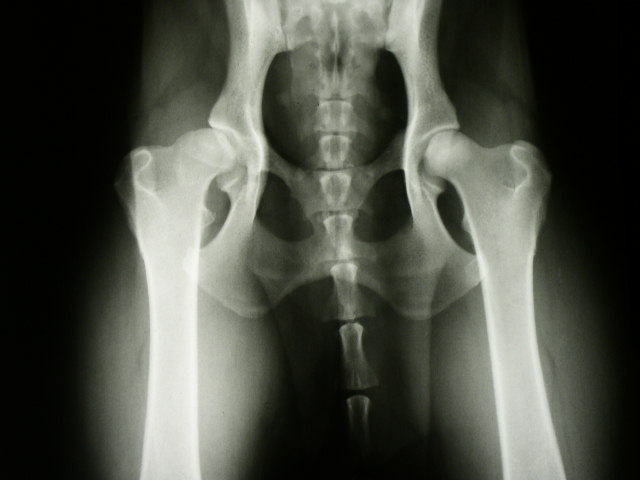

Pro zhotovení oficiálního snímku je nutná sedace psa k vyblokování svalového tonu a pro umožnění optimální polohy. Snímek se zhotovuje na zádech, s nataženými a mírně vtočenými pánevními končetinami, kyčelní klouby, kolena i hlezenní klouby uvedeme do extenze. Končetiny musí probíhat paralelně, tak, aby čéšky byly na snímku uprostřed stehenní kosti. Pánev nesmí být rotovaná.

Na snímku se hodnotí tvar hlavice, hloubka zanoření hlavice, symetrie kloubní štěrbiny, Norberg - Olssonův úhel, degenerativní změny.